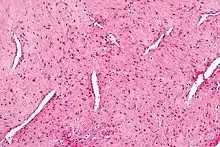

| Micrograph of a nasopharyngeal angiofibroma H&E stain. | |